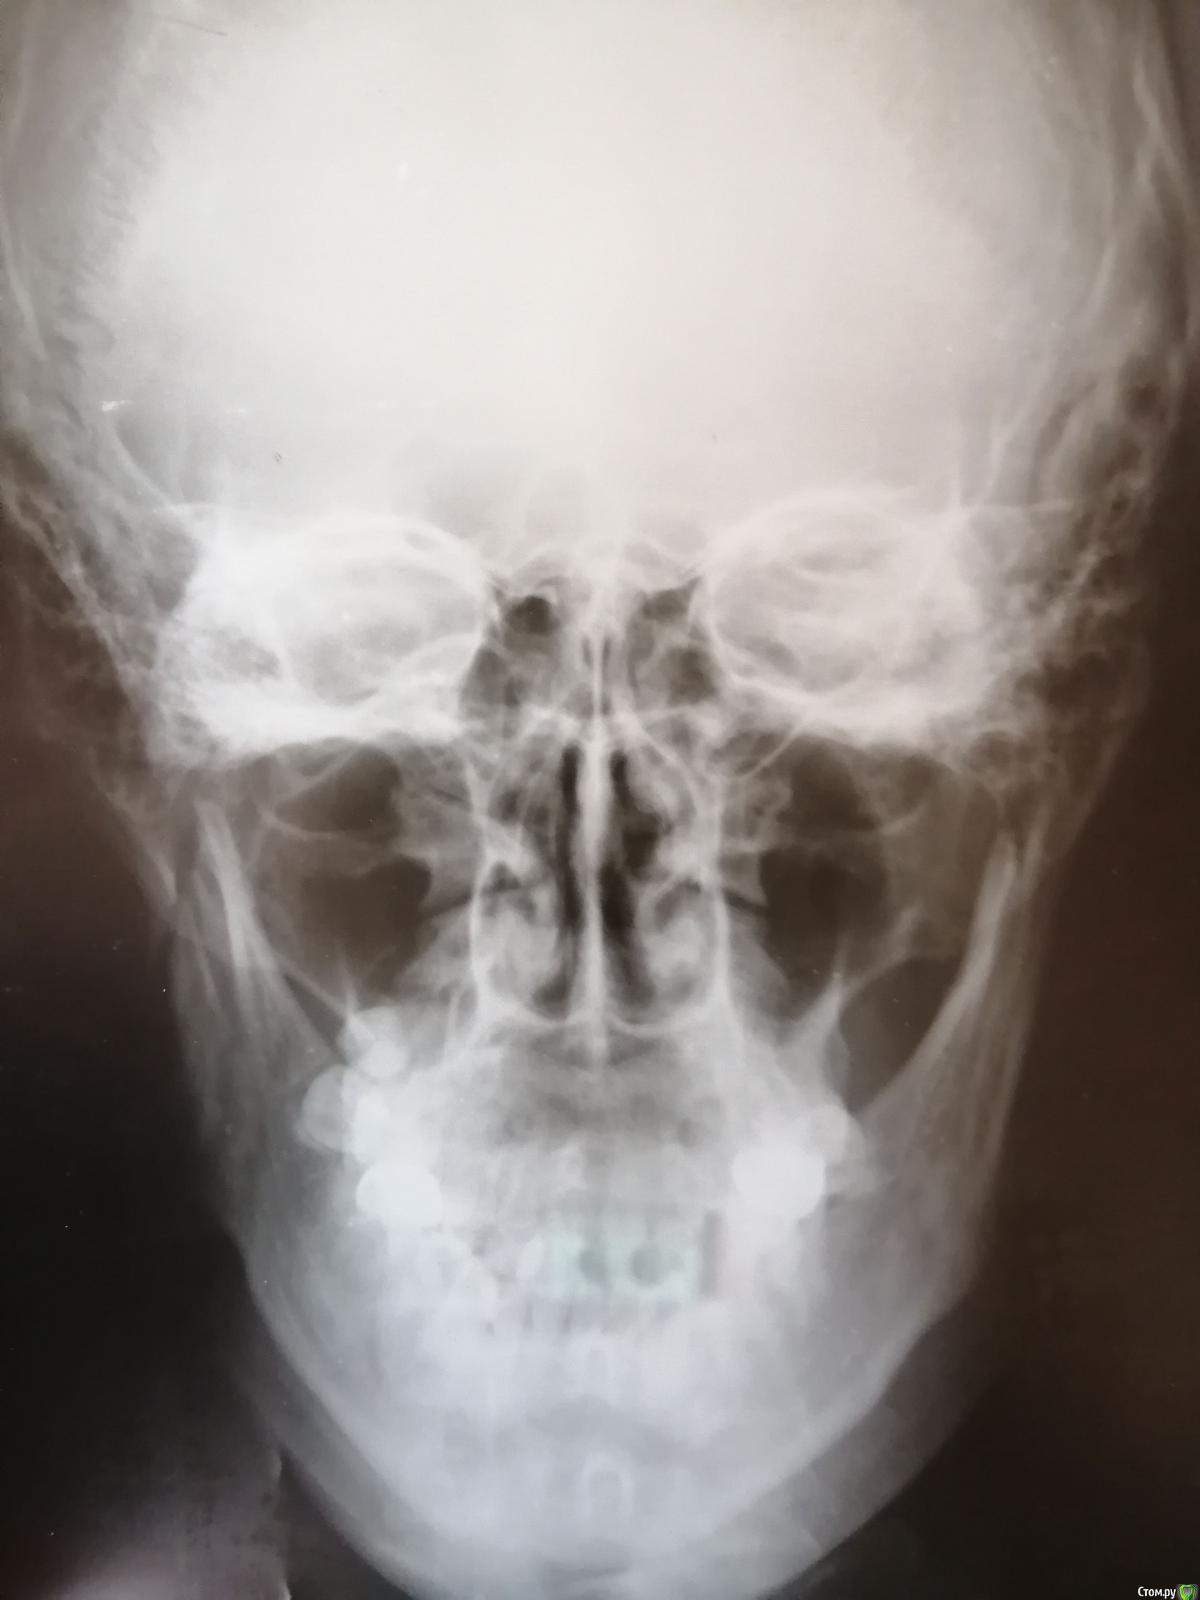

Blazingstar Опубликовано 25 июля, 2019 Поделиться Опубликовано 25 июля, 2019 Здраствуйте, посмотрите снимок, шинировали 21 июня сняли 16 июля, этот перелом не повлияет ли на что то? Операцию не делали Ссылка на комментарий

Blazingstar Опубликовано 25 июля, 2019 Поделиться Опубликовано 25 июля, 2019 (изменено) Здраствуйте, посмотрите снимок, шинировали 21 июня сняли 16 июля, этот перелом не повлияет ли на что то? Операцию не делали, по рентгену видно ли симметричность лица? Изменено 25 июля, 2019 пользователем Blazingstar Ссылка на комментарий

Irouil Опубликовано 27 декабря, 2017 Поделиться Опубликовано 27 декабря, 2017 Само по себе ничего, обычно, не воспаляется. Надо искать причину. Думается лимфоузел. Без осмотра сложно сказать больше. Первичного инфекционного очага нет, вторичный очаг в мягких тканях может быть где угодно и чем угодно. признаков хронического костного воспаления не вижу. Ссылка на комментарий